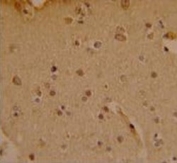

IHC analysis of FFPE human brain stained with SOX4 antibody